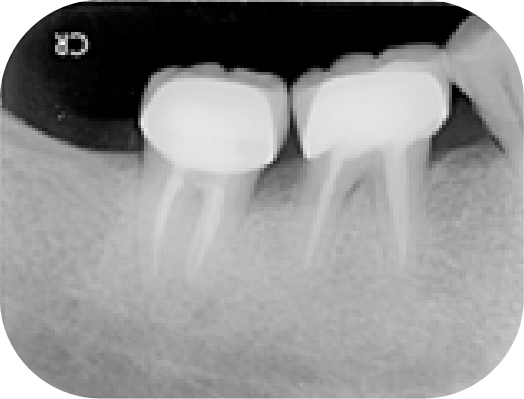

病人左下最後兩顆大臼齒在多年前有做過根管,重新治療時因為有顯微鏡輔助可以將之前清潔不下去的根管順利處理好。